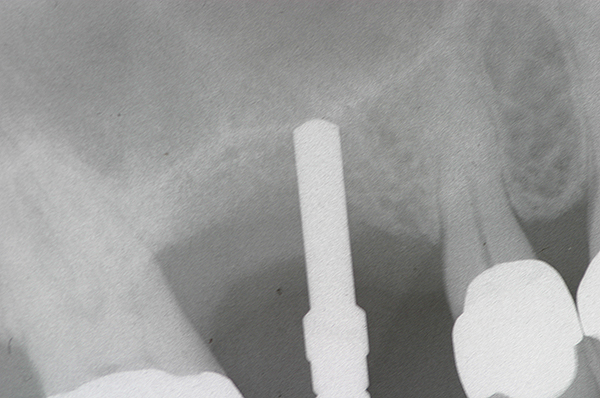

Fig 14. Radiograph of sinus composite bone augmentation in the No. 14 position.

Figure 14

Fig 15. Radiograph of implant No. 14 with sinus augmentation, day of placement. The floor of the sinus has been raised about 7 mm to 8 mm.

Figure 15

A 74-year-old man presented with only about 2 mm to 3 mm of native bone below the sinus in the No. 14 position (Figure 13). The composite graft used was an approximately 50:50 mixture of DFDBA (Bio-Oss®, Geistlich Biomaterials, www.bio-oss.com) with the addition of about 40% calcium sulfate by volume (Figure 14). The implant placed (Figure 15) was a 10-mm long, rough-surfaced, platform-shifting implant (tapered 4.2 mm to 2.8 mm), and the sinus was raised about 8 mm. The postoperative radiograph taken at 4 months (Figure 16) showed some shrinkage of the graft, but no demarcation of the old sinus floor in the area.